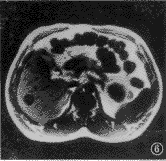

图5,6 患者 女,43岁。右叶血管瘤。反相位序列(TR 128 ms,TE 2.7 ms,翻转角70°)示低信号血管瘤周边环状高信号带(图5),而在同相位(TR 128 ms,TE 5.3 ms,翻转角70°)上病变周边呈等信号(图6)